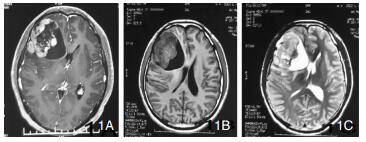

病例:患者男,26岁,因头晕头痛不适于2011年11月初次就诊,查体无异常,头部MRI提示右额叶囊实性异常信号。术中见肿瘤灰黄色,质地不均,伴有囊变,囊液黄色,完整切除病灶。术后病理倾向于孤立性纤维瘤,免疫组化:GFAP(-), Syn(-)bcl-2(+), ki-67(10%), Vim(+), EMA(+), HMB45(-), CK(-), S-100(-), CgA(-), Des(-)。

| 图 1 示第一次术前MRI |

|